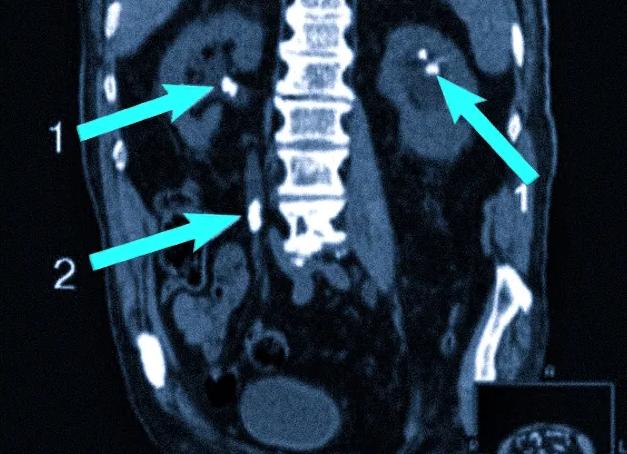

Так выглядит поликистоз почки на КТ: слева стрелками отмечены множественные простые кисты почки, не имеющие в своем составе как мягкотканого компонента, так и кальцинатов (Bosniak 1). Справа отмечена киста, содержащая в своей структуре кальцинат (Bosniak 2). Данная киста требует УЗ-контроля (или КТ-контроля) с определенной (раз в 6 месяцев) периодичностью.